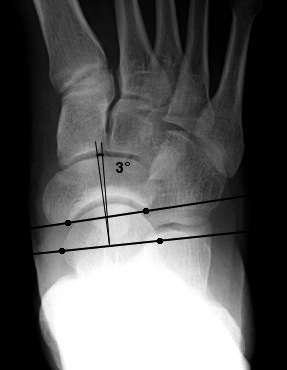

Loss of the normal straight line relationship with mearys angle 40 convex downwards. Different parameters have been described to assess talar head uncoverage including the anterior talus first metatarsal angle normal 00 to 200 talonavicular coverage angle normal70 talonavicular uncoverage percent normal 10 to 30 and lateral incongruency angle normal 50260. For example a s hoe insert used for the flat foot is designed based on the degree of flatness. Flat feet also called pes planus or fallen arches is a postural deformity in which the arches of the foot collapse with the entire sole of the foot coming into complete or near complete contact with the ground.

Syndesmosis rid6088 injury. A pediatric pes planus results in hindfoot valgus as defined by the angle formed by the leg and heel. 10 200 indicative of pes planus when 180. In normal feet the relationship between the talus and the 1 st metatarsal results in a straight line being formed along their axes ie.